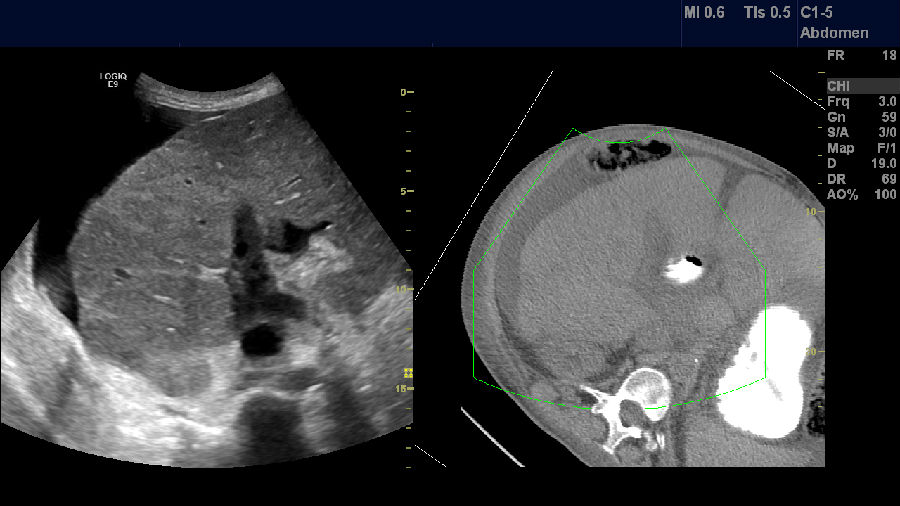

肝硬化,容积导航

肝硬化,栓子,腹水,容积导航融合成像